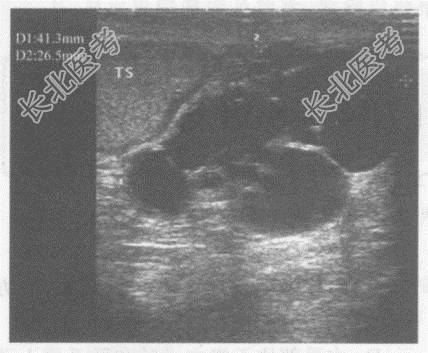

- 单项选择题临床资料:男, 56岁,黑人(赞比亚)。自诉阴囊肿胀不适20年余。

超声综合描述: 左侧睾丸足侧外可见4.3cm×2.7cm无回声区,形态不规则, 内见完整及不完整分隔,透声清亮, 包膜完整。

超声提示: A、左侧睾丸囊肿

B、左侧附睾旁囊肿

C、左阴囊内血肿

D、左侧睾丸鞘膜积液

E、左侧增生